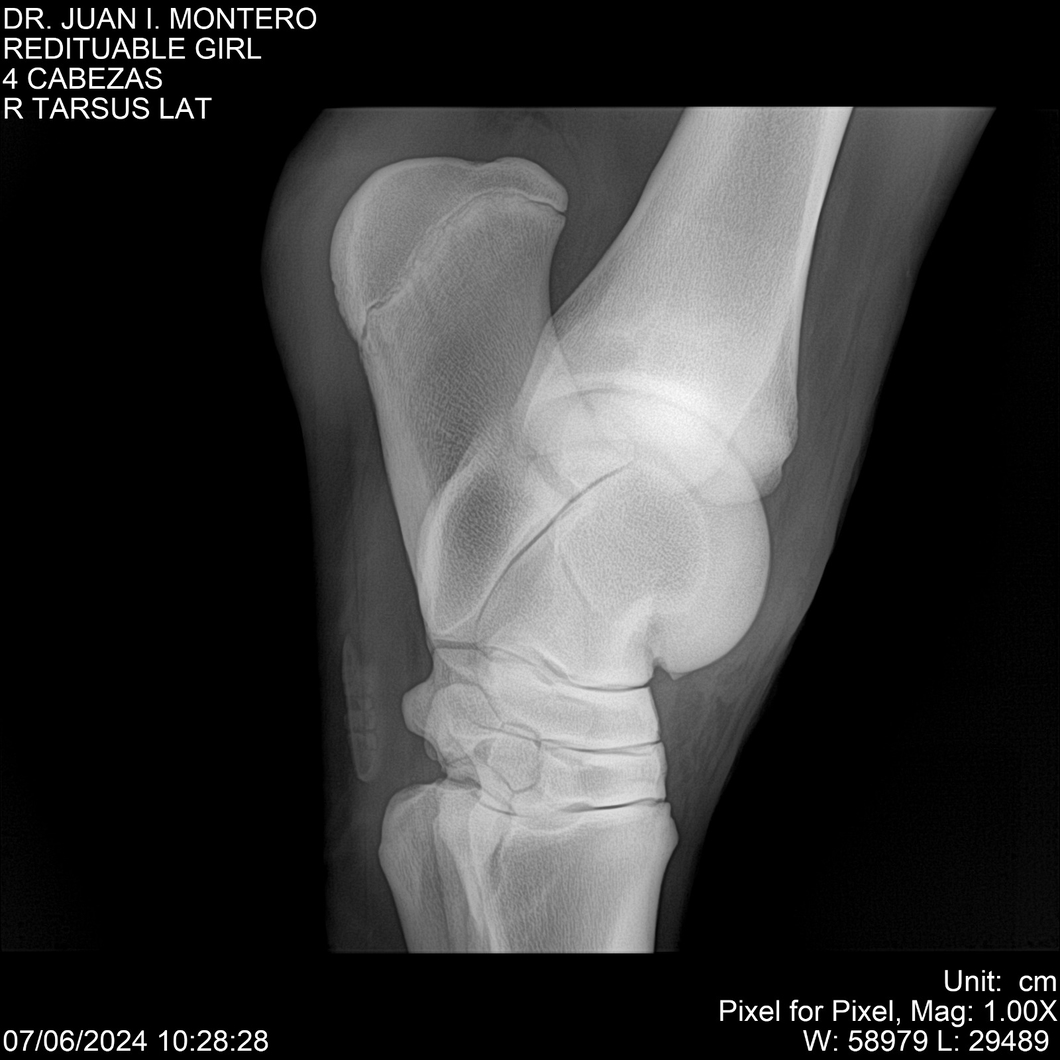

LOTE 19, REDITUABLE GIRL Lote Anterior Volver al remate Lote Siguiente Ficha Contacto Montevideo - Ficha del Lote Identificador: #281096 Categoría: Yeguarizos Montevideo - 79 Visualizaciones ClicData Contacto Empresa: Abelenda N. R., Walter Hugo Nombre*: Teléfono* : E-mail* : Mensaje Enviar Registrese gratis Este contenido Exclusivo está disponible sólo para usuarios registrados Ingresar